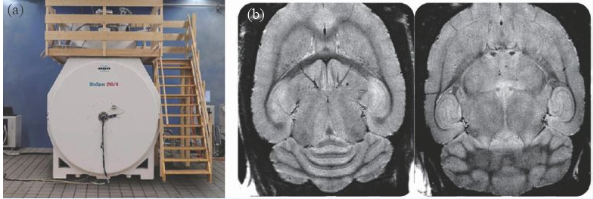

除了人體成像的超高場磁共振成像裝置外,用于動物臨床前應用的裝置在磁場強度上遠遠走在了前面,10 年前就出現了16.4 T/26 cm動物成像MRI 機,德國的Bruker公司在幾年前也推出了更高磁場的動物成像機—— 21 T/11 cm動物成像MRI機(圖8)。

圖8 (a)21 T MRI磁體;(b)大鼠的腦部高分辨率成像(分辨率26 μm)